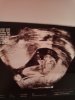

Hej dziewczyny. Mam.pytanie. Podczytuje Was i sie znacie na zdjeciach. Otoz wczesniej mialam w brzuchu dziewczynke. Pozniej lekarz nie byl pewny. Tydzien temu nie.byl pewny. Poszlam.prywatnie. I inny lekarz zobaczyl chlopca. Tylko ja mam.pytanie co to jest nad tym sisiakiem. Na koniec wizyty jak nagrywał zdjecia na plyte zapytal czy znalam plec. Tak jakby sobie gdybal.